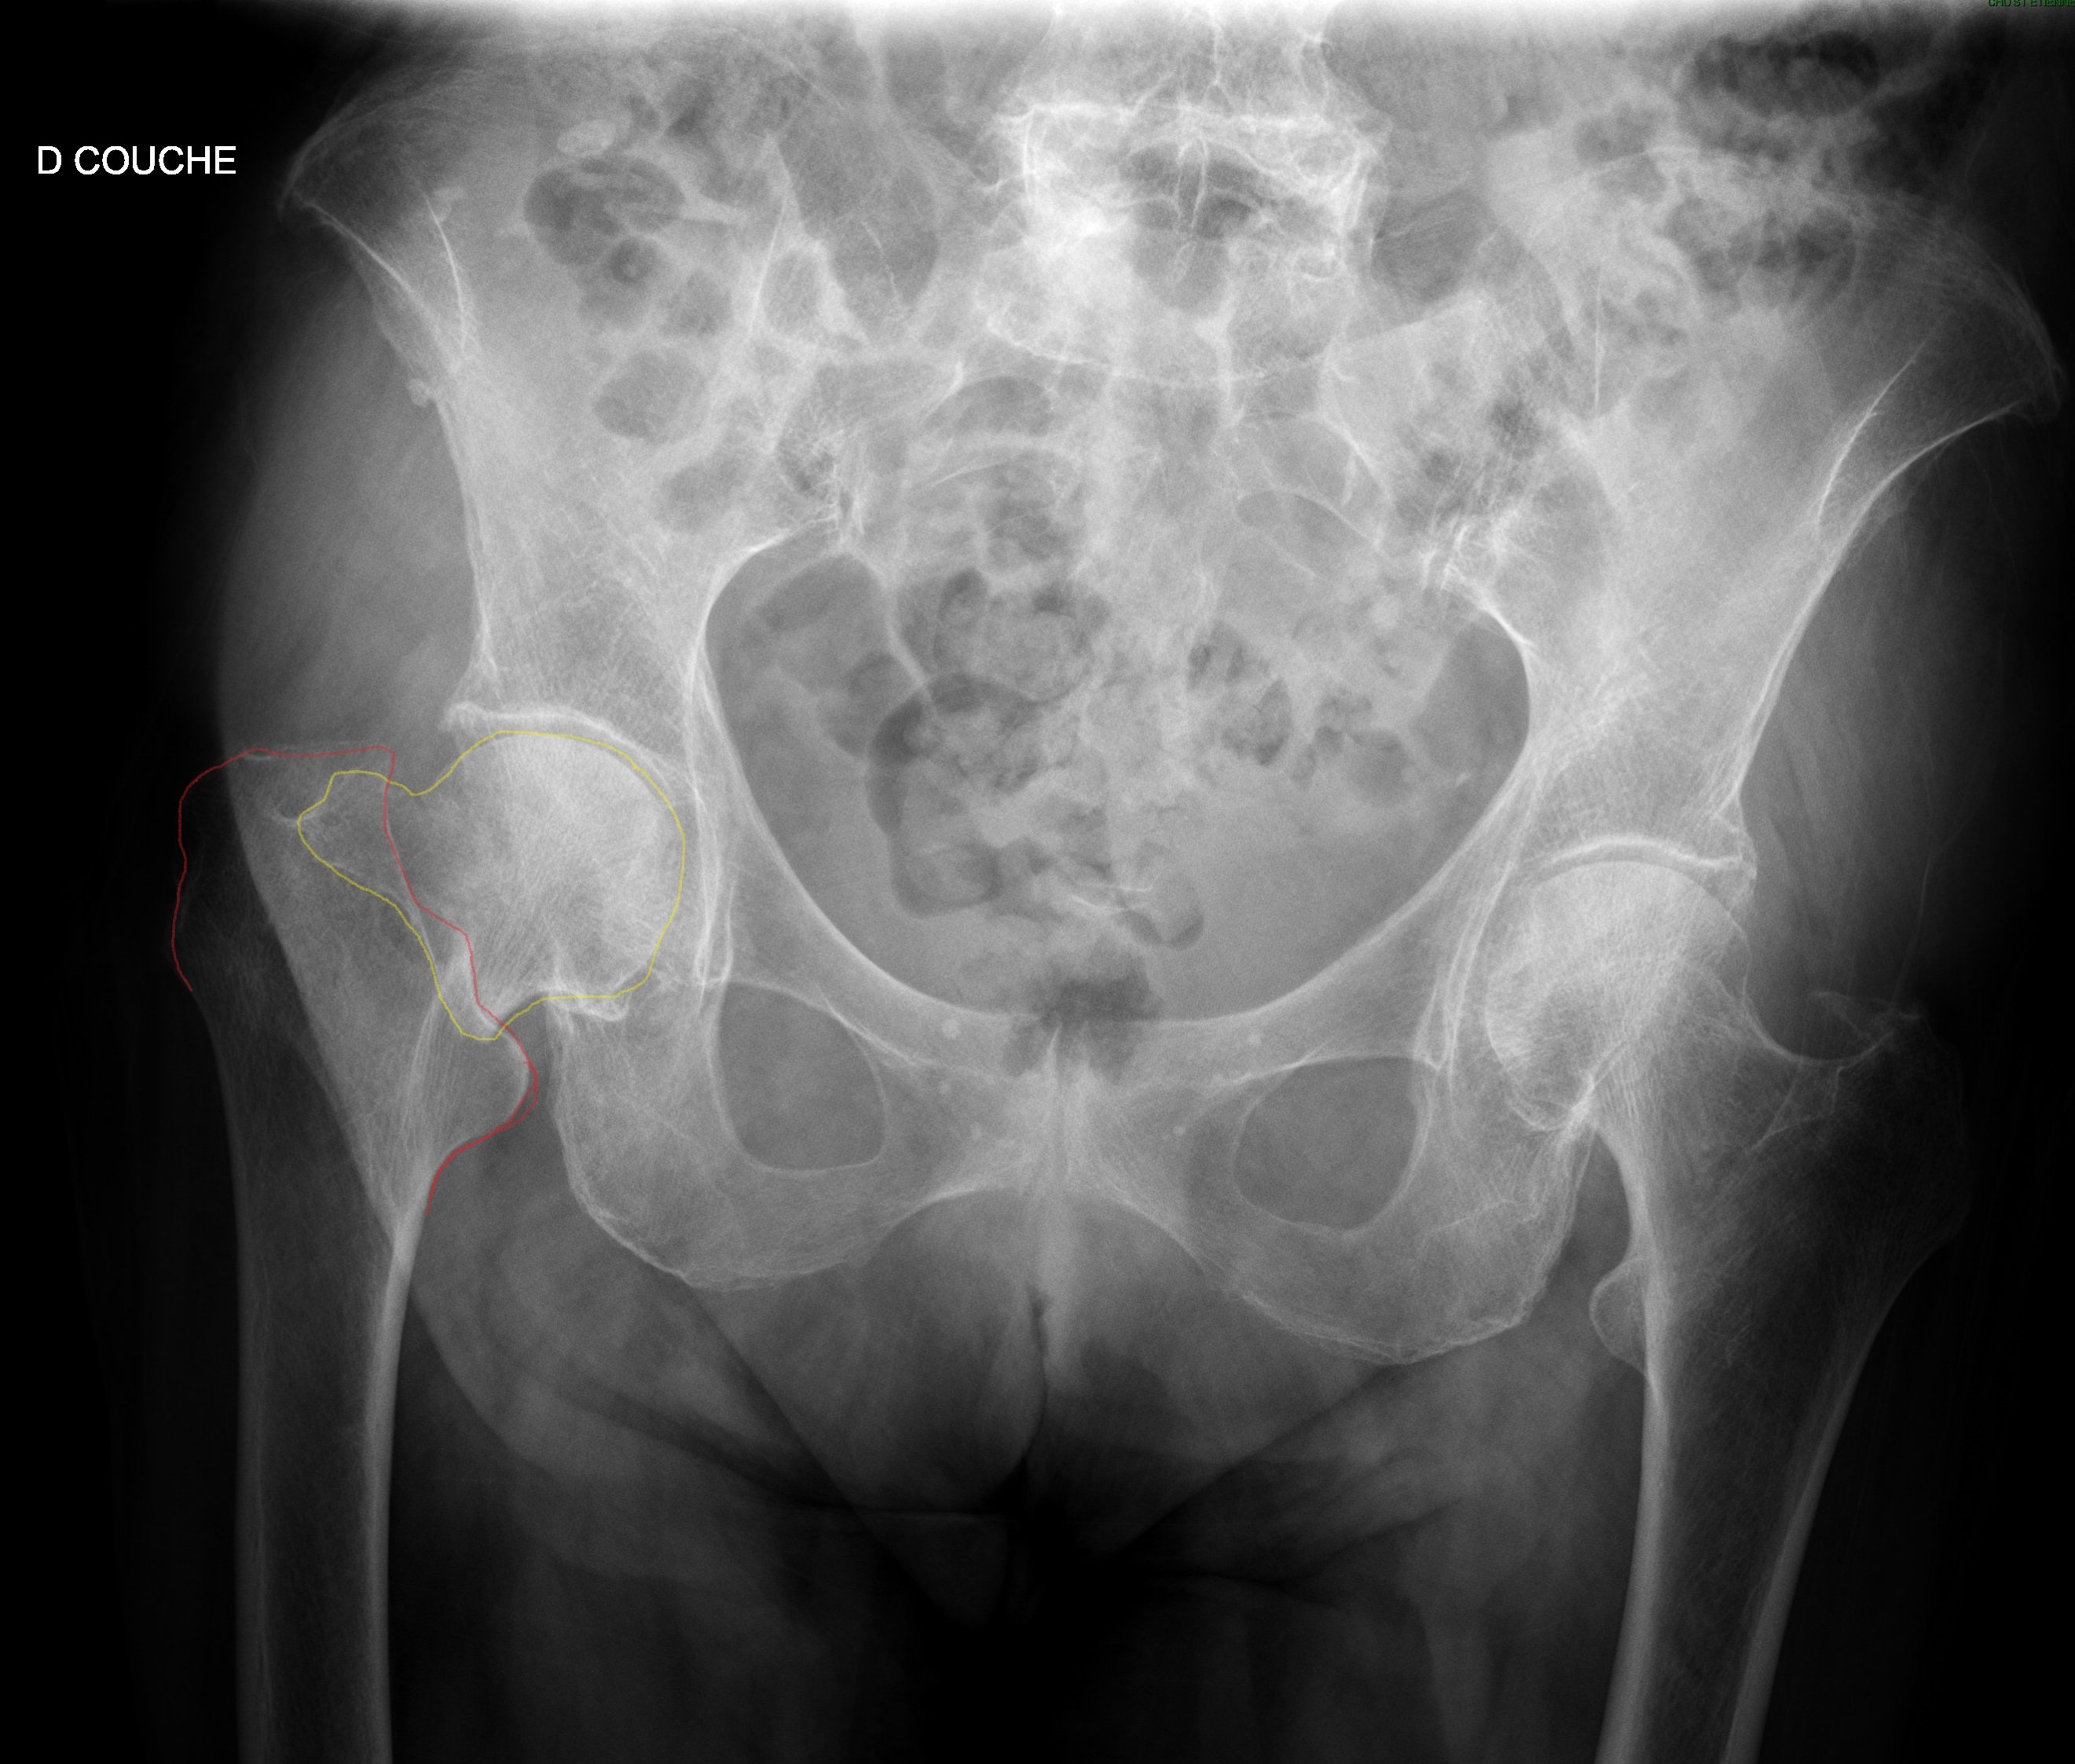

Garden 4 car il n'y a plus de continuité entre la tête et le col (regarde bien tu devines le trait de fracture de la tête derrière le col, je sais pas si je suis clair)

Coxa valga avec contact = garden 1

Ni l'un ni l'autre avec contact = garden 2

Coxa vara avec contact = garden 3

Plus de contact = garden 4

Voila schématiquement comment classifier en 2 secondes, apres y a d'autres mots clés à apprendre sur chaque stade

En fait la j'ai un peu galere à differencier entre Garden III et IV, je vois pas bien en quoi sur cette radio on peut dire qu'il y'a une rupture cervicale totale ..